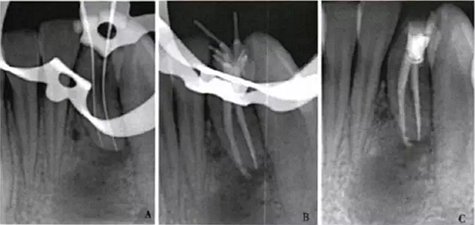

1周后,患者述疼痛消失。復診采用冷測壓方法根管充填(圖2),牙冠開髓孔處應用Chem—flex(DentsplyDeTreyGmbH,Konstanz,Germany)充填。由于患牙牙冠形態(tài)異常,且唇側(cè)形態(tài)尚未恢復;患牙周圍有牙石、軟垢,建議患者行牙周及修復治療以維持長期療效,被患者拒絕。9個月后隨訪,患者自述患牙經(jīng)治療后無癥狀,臨床檢查見32叩診正常,無松動;影像學檢查見32根尖周圍透射區(qū)域明顯減?。▓D3)。

A:32術中片確定根管工作長度;B、C:32術后片示根管充填適充

圖2 32根管治療x線片